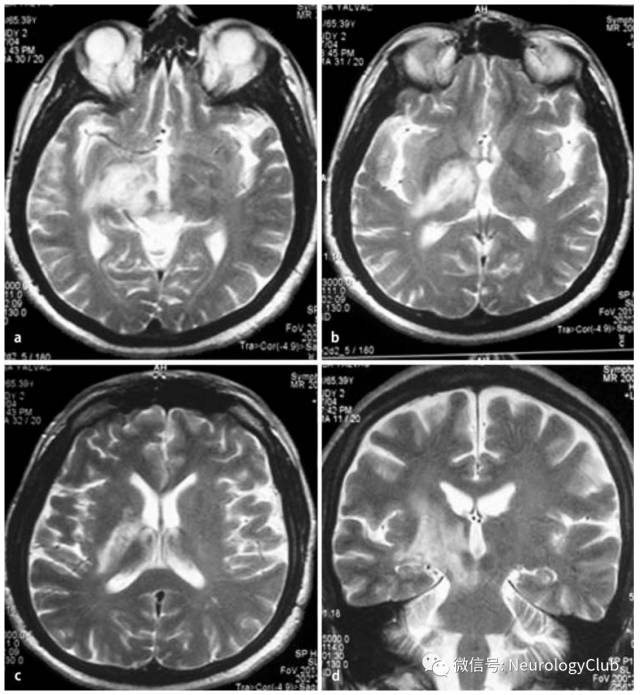

神经白塞病包括实质型和非实质型。实质型神经白塞病约占70-80%,病灶以脑干(脑桥、中脑)常见,也可延伸累及间脑、基底节区。累及大脑半球时,常为多发的小白质病变,也可表现为孤立性类瘤样病灶。脊髓受累时可见单发或多发的不同长度的炎性病变,常位于颈胸髓。也可有脑膜脑炎,表现为脑膜强化。急性期病灶在T1WI上呈等-低信号,增强通常为片状强化,也可出现环形强化,T2WI和FLAIR上为高信号,DWI上高信号,相应ADC值降低。部分病灶中心或周围可见出血。累及脊髓时横断面T2WI可见“百吉饼(在美国纽约较为流行,也称硬面包圈)征(Bagel Sign)”。慢性期,病灶多缩小,通常无强化,可见脑萎缩,尤其是脑干。

(图4:FLAIR可见脑桥与中脑受累,延伸累及间脑)

(图5:T2WI可见中脑病灶,延伸累及间脑和基底节区

(图16:A-B:典型实质病变,从间脑延伸至基底节;C:多发性硬化样病灶;D:非特异性白质病变)